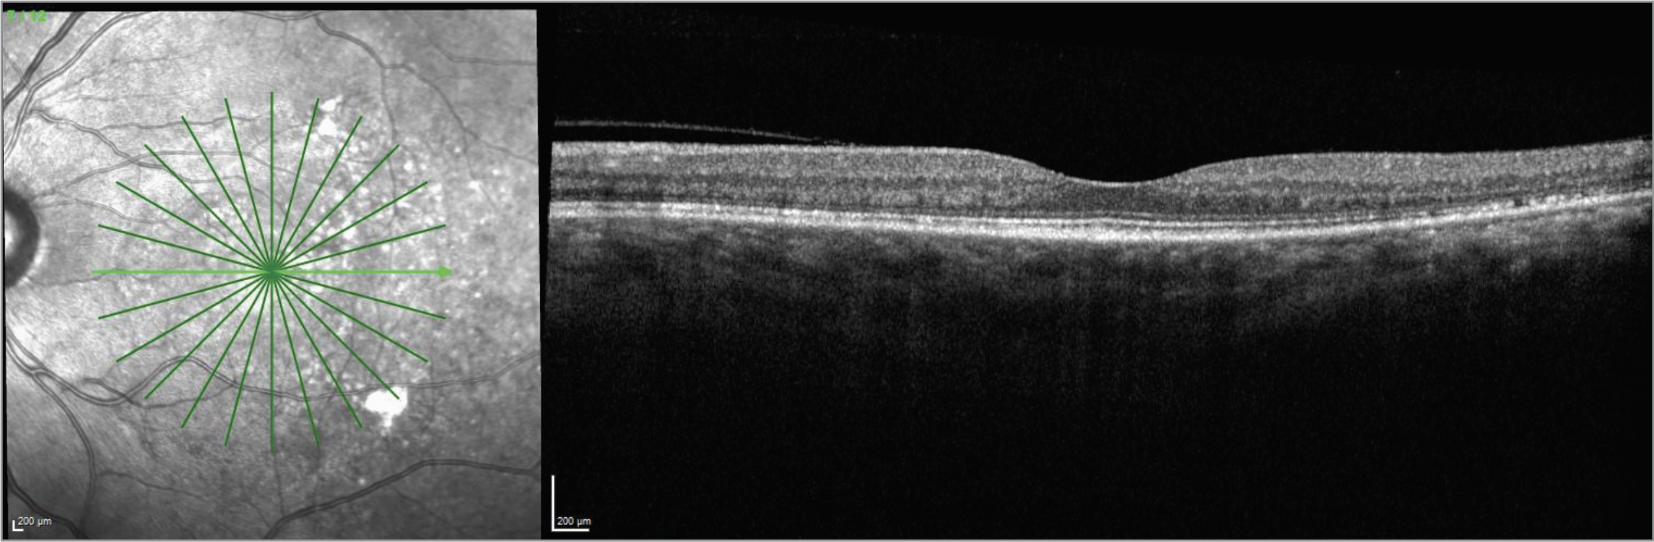

![]() |

| CaptionFigure 7. OCT of the right eye one year after stopping infliximab. |

Fundoscopic examination of both eyes demonstrated normal optic discs and normal vasculature; however, there were 360 degrees of serous choroidal detachments and large pockets of subretinal fluid throughout the macula and mid-periphery (Figures 1, 2). Fundus autofluorescence demonstrated hyperautofluorescence within the pockets of subretinal fluid in the macula and mid-periphery of both eyes (Figure 3). Fluorescein angiography revealed diffuse leakage of the peripheral vessels in both eyes and pooling corresponding to the pockets of subretinal fluid in both eyes. There were pinpoint areas of hyperfluorescence, most notable in the left eye, reminiscent of a “starry sky” appearance (Figure 4). Indocyanine green angiography revealed mixed hyper- and hypofluorescence of the macula. Optical coherence tomography of both eyes demonstrated multiple areas of large bacillary detachments in both eyes (Figures 5, 6).

In this case, the presence of a bacillary detachment was critical for making the diagnosis of VKH in a timely manner. “Bacillary” means “shaped like a rod”; a bacillary layer detachment is named as such because photoreceptors are approximately rod-shaped, and the detachment involves splitting of the photoreceptors at the level of the inner segment myoid. It can be recognized on OCT as fluid between the ellipsoid zone and the external limiting membrane.